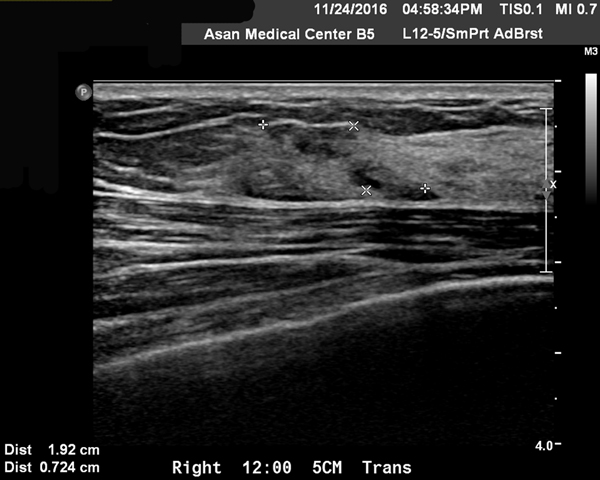

양측에 침윤성 유방암으로 수술을 하게 되었고(2017/12/26) 병기는 1기였다. 이후에 2017년 1월 말부터 방사선 치료를 양측 수술 부위에 시행하였다. 당시의 자료를 보면 다음과 같다.

0-3

수술 전의 초음파 자료에 양측에 각기 1.92×0.7cm(right breast 12시 방향 5cm 거리)와 0.69×0.51cm(left breast 7시 방향 4cm 거리)의 두개의 크지 않은 종양이 보였다.